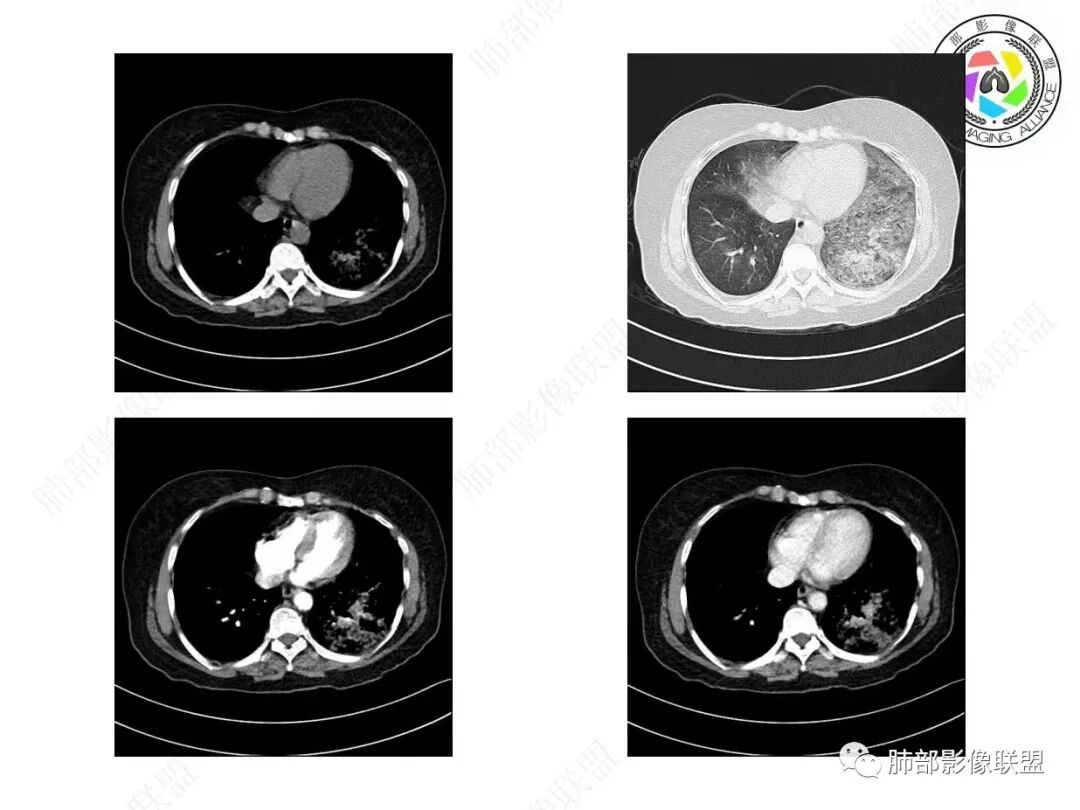

小兜:女,57岁,间断咳嗽1月,咳白色粘痰。CT示左肺下叶实变影,周围可见大片磨玻璃密度影,右肺亦见少量斑片状磨玻璃密度影。考虑恶性可能,左肺下叶粘液腺癌伴播散。

宇宙:两肺多发磨玻璃影,边缘模糊,左肺为著,左肺下叶伴实变,增强实变不均匀强化,其内支气管有阻塞、扩张,考虑粘液腺癌。

飞鹰行动:病史较长,左肺下叶实变及周围磨玻璃影,增强可见血管造影征,考虑左肺下叶粘液腺癌。

放射线:左肺下叶实变及双肺磨玻璃影,左下肺病灶周围磨玻璃影,有重力作用,呈叠瓦片状,增强可见血管造影征,考虑左肺下叶粘液腺癌伴双肺播散。

放射小白:中年女性,间断咳嗽一月余,咳痰4天;影像表现:右肺中下叶、左肺下叶见磨玻璃密度影,左肺下叶局部可见实性密度影,实性成分内部可见变窄、截断支气管通气征,增强实性成分内部可见血管造影征,但是血管扭曲,结合以上分析两肺符合肺黏液腺癌,不排除肺腺癌。

患者,女性,57岁。咳嗽1月、咳痰4天,亚急性病史,抗炎效果不佳,体温不高,痰为白色黏痰,白细胞稍高,主病灶在左下叶,实变+GGO,其余肺也有GGO,伴随有结节。

本例病例老年女性,慢性病程,抗炎效果不佳。CT示左肺下叶实变影,周围可见大片磨玻璃密度影,密度不均。右肺亦见少量斑片状磨玻璃密度影。增强可见血管造影征,结合南大分析,排除真菌,结核等,答案就呼之欲出了。